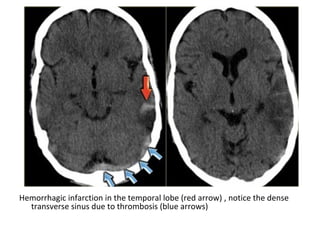

Hemorrhagic infarction in the temporal lobe (red arrow) , notice the dense

transverse sinus due to thrombosis (blue arrows)

(a) FLAIR shows the venous infarction in the temporal lobe , (b) CT nicely

demonstrates the dense thrombosed transverse sinus (yellow arrow)